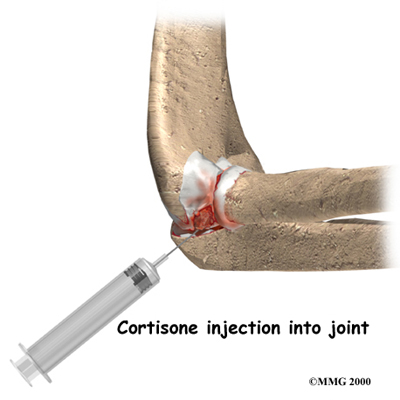

An injection of cortisone into the elbow joint can give temporary relief. Cortisone is a powerful anti-inflammatory medication. It can very effectively relieve pain and swelling. Its effects are temporary, usually lasting several weeks to months. There is a small risk of infection with any injection into the joint, and cortisone injections are no exception.